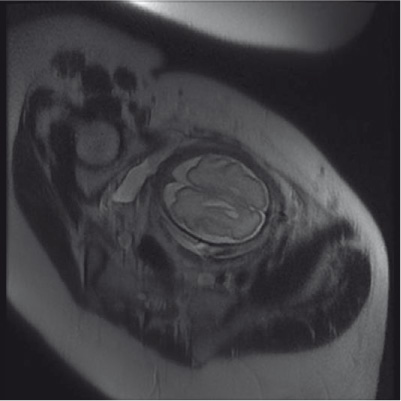

To further study the intracranial anatomy, an MRI was scheduled. MRI at 29 weeks plus 1 day confirmed, by the finding of a hypersignal in T2, the presence of cystic areas located bilaterally at the frontal periventricular germinal matrix zone, larger on the left (12 mm vs. 7 mm), with no restriction on diffusion-weighted imaging. The ventricular complex was within normal limits (Figure 3).

Prenatal MRI at 29 weeks plus 1 day.

Single-shot fast spin-echo T2 coronal image confirms the cystic-signal cerebrospinal fluid localized in the periventricular zone.